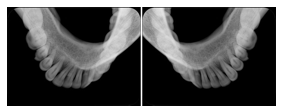

1. A patient in rural Canada visits a general ophthalmologist and is found to have diabetic macular edema. The general ophthalmologist would like to discuss the case with a retina specialist before performing laser surgery. A fluorescein angiogram is done with multiple retinal images taken in a timed series after an intravenous injection. The images along with a Structured Display are shared via a Health Information Exchange with a retina specialist in Calgary, who opens them using his Ophthalmology EMR software and consults via phone with the general ophthalmologist. Both physicians view the images in the same layout so the retina specialist can provide accurate guidance for treating the patient.

2. A patient in rural Iowa visits his primary care physician for management of diabetes. Three non-mydriatic (patient's eyes are not dilated) photographs are taken of the back of each eye, and forwarded electronically along with a Structured Display to an ophthalmologist in Iowa City. The ophthalmologist reads the photos in an agreed upon layout so there is no mistake about what portion of which eye is being viewed. The ophthalmologist is able to tell the primary care physician that his patient does not need to come to Iowa City for face to face ophthalmologic care, but that there is a particular view of the left eye that should be photographed again in 6 months.

Ophthalmic Retinal Study Structured Display

Figure OO-3. Ophthalmic Retinal Study Structured Display